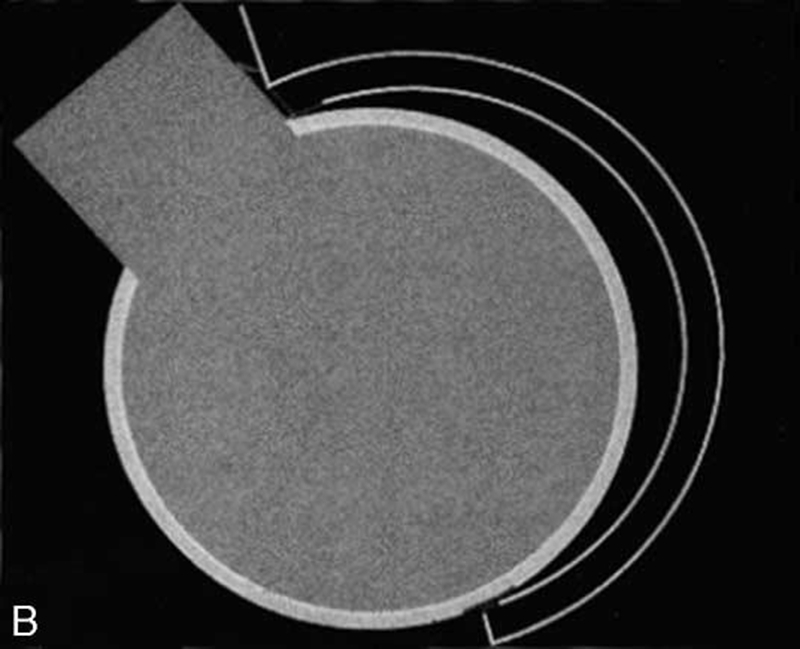

第二类:钳夹型撞击(pincer impingement),由于髋臼过度覆盖股骨头引起。钳夹型撞击股骨头颈结合区的形态基本正常,主要是因为髋臼前方的过度覆盖导致。存在这种畸形的患者,在极度屈髋活动中发生股骨和髋臼的撞击,进而引起髋关节盂唇和髋臼软骨发生损伤。

图2 文献中图片,展示钳形撞击

钳夹型撞击患者的盂唇和软骨损伤的范围相对比较局限,但是凸轮型撞击患者造成的盂唇和软骨损伤相对范围比较广泛。在日常的临床工作中,其实多数我们碰到的患者为两者的混合型撞击。